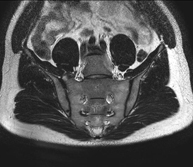

- RM de Sacroilíaques

Prova diagnòstica no invasiva que consisteix en l'obtenció d'imatges d'alta definició anatòmica de les articulacions sacroilíaques mitjançant l'ús d'un camp electromagnètic i ones de ràdio (amb un emissor i un receptor). No utilitza radiació ionitzant. Indicacions: dolor sacroilíac inflamatori. - RM ATM (Articulació temporo-mandibular)

Exploració per a l'estudi de lesions a tendons, músculs i articulacions coxofemorals. Permet identificar de manera precoç l'artrosi de maluc. Resulta molt útil per detectar les bursitis i l'osteopatia dinàmica de pubis, freqüent en esportistes. La durada aproximada és de 20 minuts. No utilitza radiació ionitzant. - RM de Sacroilíaques

Estudi específicament dissenyat per valorar aquestes articulacions i la seva inflamació en els pacients que pateixen espondilitis anquilosant. També resulta d'utilitat en pacients amb traumatismes i possibles fractures del sacre i el còccix. La durada aproximada és de 16 minuts. No utilitza radiació ionitzant. - RM de Glutis